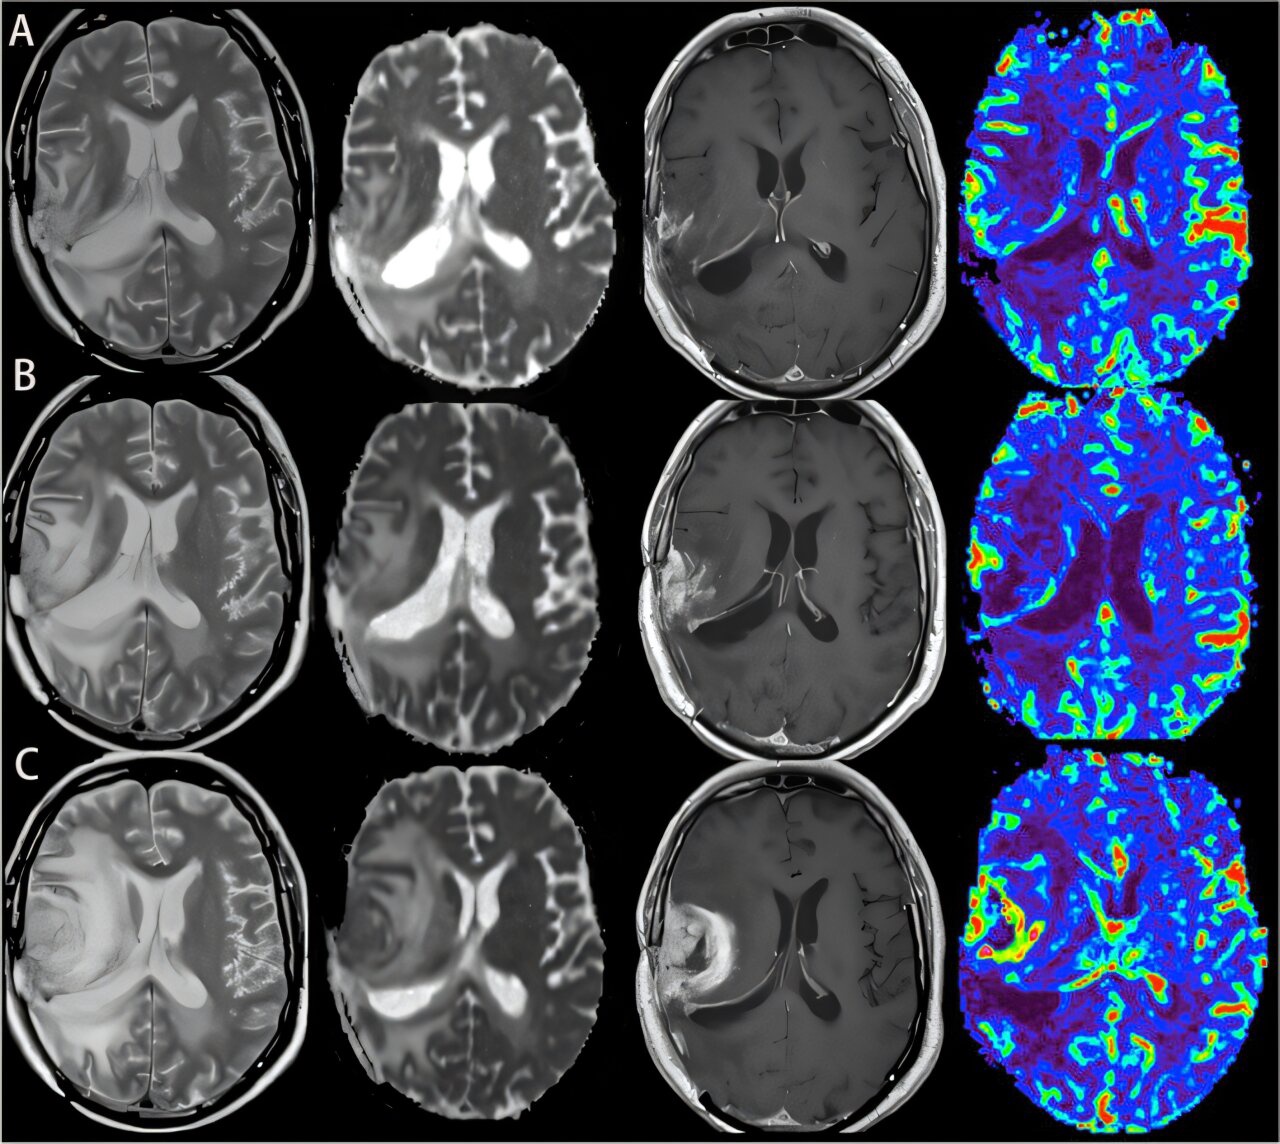

The findings recast the cancer as interacting with skull-to-brain immune channels rather than acting only within the brain.